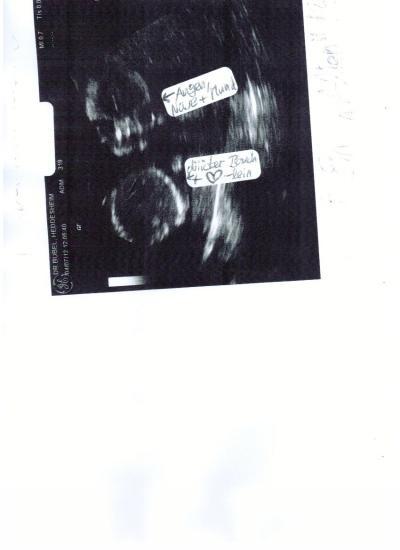

Hallo liebe Bald-Mamis, ich komme aus dem Dezember-Bus und halte mal eben hier bei euch an, da ich denke, dass ihr Erfahrungen habt in Puncto "US-Outing" Könnt ihr auf dem aktuellen US-Bild unseres kleinen Aliens einen Hinweis auf das Geschlecht erkennen? Danke, euch allen ALLES GUTE und LG, Julie

Meiner Meinung nach erkennt man auf dem Bild kein geschlecht. Weil beim Bauch ist doch dann Schluss und man sieht nicht mal die Beine...

ja...das wollt ich auch Grad sagen...man sieht nichts...nur des Bäuchlein.

Ich seh da auch nichts :) Was hat denn der Arzt gesagt? Liebe Grüße

...nun lächelte mich meine Gyn vergangenen Mittwoch an und meinte nur: "Na, bzgl meiner ersten Vermutung bin ich mir ja gar nicht mehr sicher." Ich fragte, zu "was" sie denn nun tendieren würde, doch sie meinte, wir sollten die Feindiagnostik abwarten. SICHER würde sie das Geschlecht nur dann nennen, wenn sie sich selbst tatsächlich zu 99% sicher sei... Sie gab mir das US-Bild in die Hand und meinte: "Schauen Sie es sich ruhig mal ganz genau und in Ruhe an." Hm, und nun raten und überlegen mein Schatz und ich -ebenso unsere 3 Kinder, die als Ü-Eier im Bauch auf den US-Bildern sehr deutlich zu sehen waren -> nur bei unserem kleinen Sohn hieß es anfangs "zu 99% ein Mädchen", was in der Spät-SS korrigiert wurde...dann jedoch durch offensichtliches Zeigen seines Pullermanns sehr deutlich ...- Ratet ihr noch mit? ALLES LIEBE EUCH ALLEN, DANKE und LG, Julie

Huhu! Also ich würde bei dem Bildchen auch noch keine Prognose abgeben. Ist noch viel zu früh um sich da festzulegen und wirklich erkennen kann man auch nichts. Das was man als Geschlecht identifizieren könnte, is so vage.... da kann auch gut die Nabelschnur für was anderes gehalten werden. Wir lassen uns bei unserem Zweiten überraschen und haben ja nur noch ein paar Wochen. Dann wissen wir es sowieso sicher. Viel Spaß beim weiterrätseln Übrigens ein süßes Bildchen!

hallo,schleiche mich mal aus dem oktober-forum rein und erkenne auf dem bild einen JUNGEN!!!!